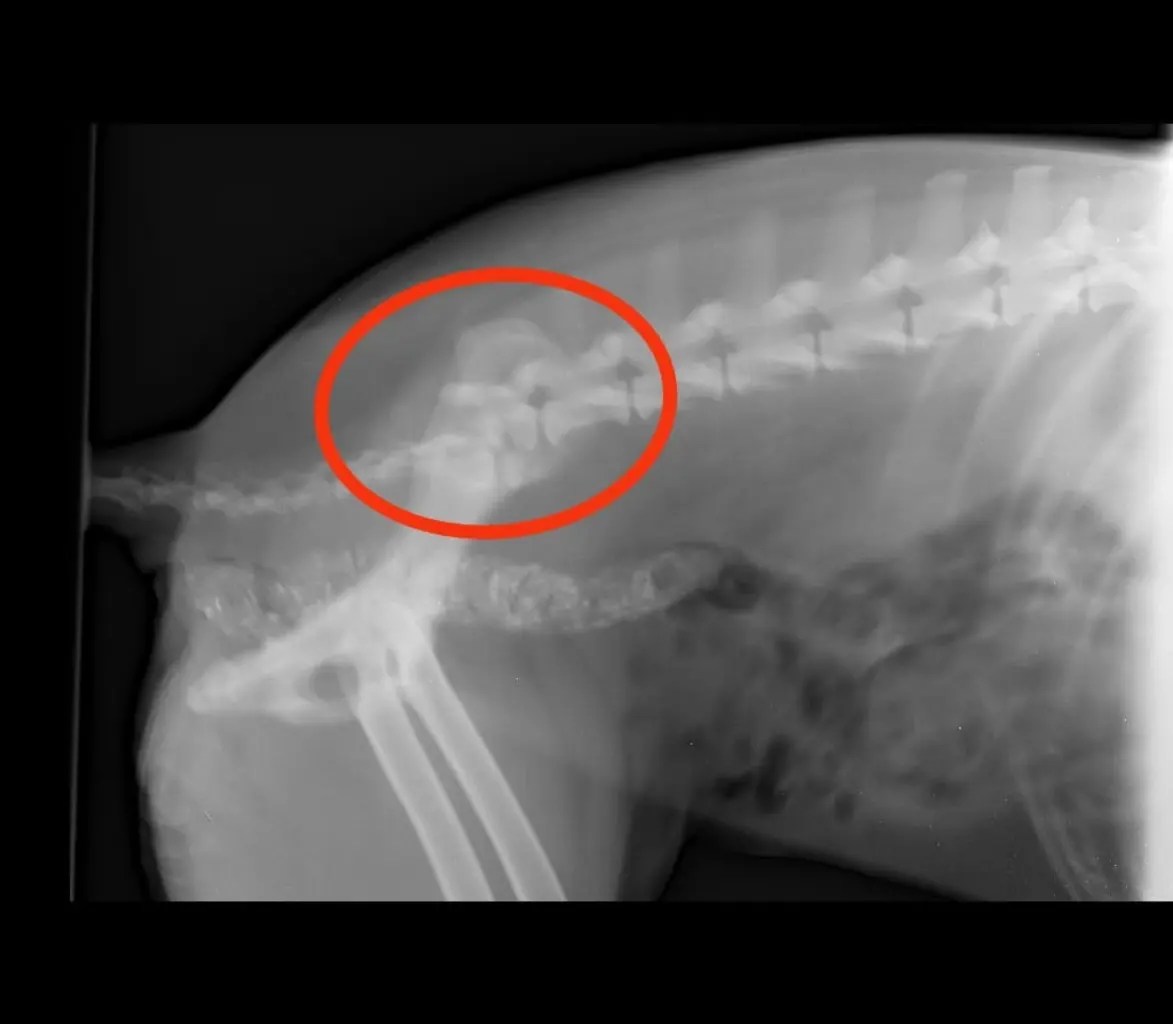

Somehow came back this morning and wasn’t able to walk. We sent her for a check up, xray etc as soon as we could.

The second slide Is her xray. Major break in the spine.

It’s a wait and watch situation. Medication for the first three days to manage her pain and cage rest because she isn’t allowed movement. Hoping she’s able to poop and pee , or else, there is little hope ๐